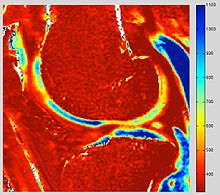

dGEMRIC T1 Map of knee cartilage

dGEMRIC T1 Map miliseconds